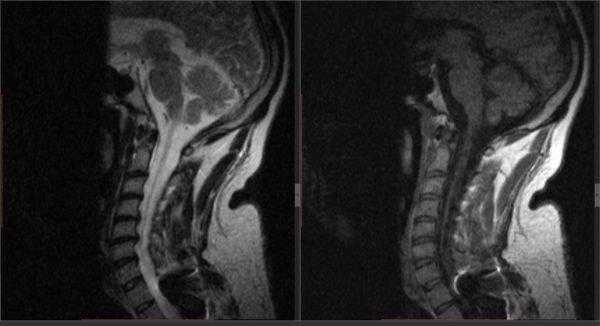

- Томографии. В случаях, когда ассимиляция атланта сопровождается симптомами поражения продолговатого мозга, необходимо исключение другой церебральной патологии: опухоли головного мозга, сирингомиелической кисты, абсцесса. С этой целью проводится КТ или МРТ головного мозга, которые в случае ассимиляции атланта могут выявлять признаки гидроцефалии. МРТ позвоночника позволяет судить о степени сдавления спинного мозга.

Рентгенологические методы диагностики могут выявить трофические проявления сирингомиелии в виде остеопороза, разрушения костных элементов сустава и т. п. Точно диагностировать сирингомиелию позволяет МРТ позвоночника, а при невозможности ее проведения - миелография. Эти методы обследования дают возможность увидеть сирингомиелические полости в спинном мозге и стволе.